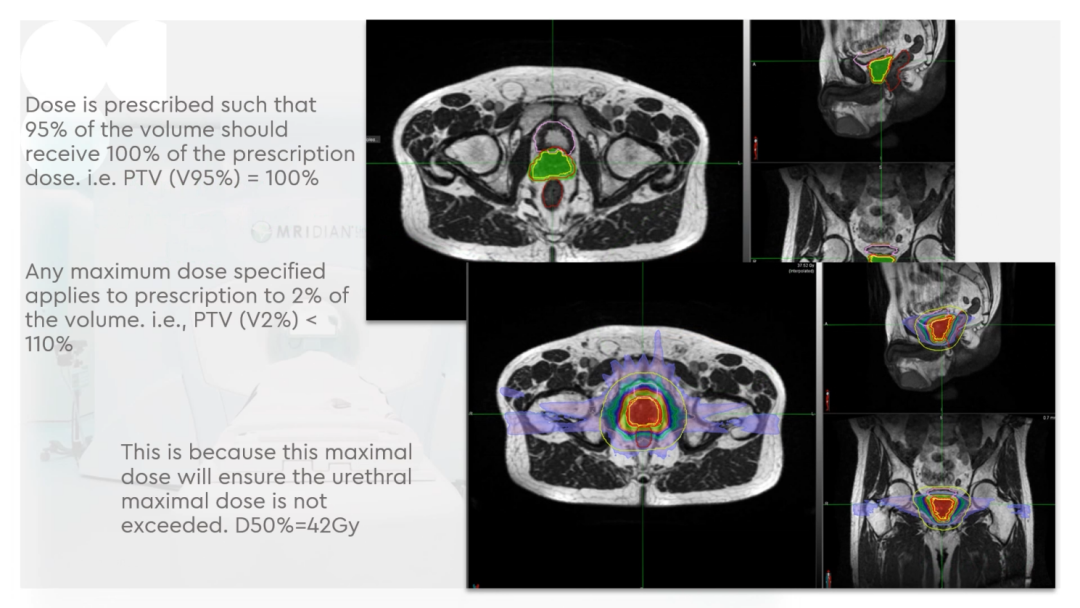

Dr. CamilleriÌåÏÖ£¬£¬£¬£¬£¬£¬£¬ËûÃÇÔÚ×öÔÚÏß×Ô˳Ӧ·ÅÁƵÄʱ¼ä£¬£¬£¬£¬£¬£¬£¬ÎªÁËÌá¸ßËÙÂÊ£¬£¬£¬£¬£¬£¬£¬½ö¶Ô°ÐÇøÍâ·Å3cmÒÔÄÚµÄΣ¼°Æ÷¹ÙµÄת±ä¾ÙÐÐ×Ô˳Ӧµ÷½â»òÖØÐ¹´»ÂÖÀª£¬£¬£¬£¬£¬£¬£¬¼ûFigure 13¡£¡£¡£¡£¡£¡£ÕâÑù¿ÉÒÔËõ¶ÌÂÖÀª¹´»µÄʱ¼ä¡£¡£¡£¡£¡£¡£¹ØÓÚ·ÅÁÆÍýÏ룬£¬£¬£¬£¬£¬£¬Ê¹µÃ95%µÄ°ÐÇøÌå»ý½ÓÊܵ½100%µÄ´¦·½¼ÁÁ¿ÁýÕÖ£¬£¬£¬£¬£¬£¬£¬²¢½«×î´ó¼ÁÁ¿ÏÞÖÆÎª2%µÄ°ÐÇøÌå»ý²»Áè¼Ý´¦·½¼ÁÁ¿µÄ110%£¬£¬£¬£¬£¬£¬£¬ÕâÑù¾ÍÄܰü¹ÜÔÚͼÏñÉϺÜÄÑÏÔʾµÄÄòµÀ²»»á³¬Á¿£¬£¬£¬£¬£¬£¬£¬¼ûFigure 14¡£¡£¡£¡£¡£¡£ÁíÍ⣬£¬£¬£¬£¬£¬£¬ÔÚÖÆ×÷·ÅÁÆÍýÏëʱ£¬£¬£¬£¬£¬£¬£¬½«PTV·ÖΪPTV LOWºÍPTV High£¬£¬£¬£¬£¬£¬£¬PTVºÍΣ¼°Æ÷¹ÙÖØµþµÄ²¿·ÖΪPTV LOW£¬£¬£¬£¬£¬£¬£¬½«PTV LOWµÄ¼ÁÁ¿Ä¿µÄÉ趨ÔÚΣ¼°Æ÷¹ÙµÄÄÍÊܼÁÁ¿ÒÔÏ£¬£¬£¬£¬£¬£¬£¬ÕâÑù¾ÍÄܰü¹ÜΣ¼°Æ÷¹Ù²»³¬Á¿£¬£¬£¬£¬£¬£¬£¬¼ûFigure 15¡£¡£¡£¡£¡£¡£